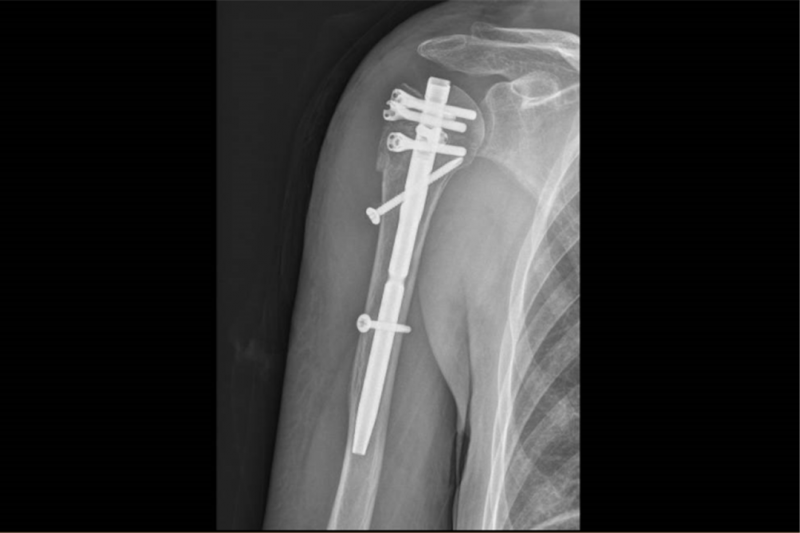

术前,将患者骨折部位的薄层CT扫描影像学数据进行三维重建,据此打印出骨折模型。手术时,医生按照术前设计,有条不紊地开展手术,将肱骨髓内针植入。术后,患者的肩关节功能正常,恢复良好,达到了此前预期的创伤小、恢复快以及减少围术期并发症等目的。

患者的术后影像。